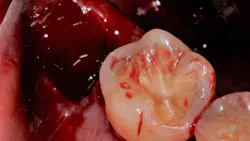

- Pack the socket with a hemostatic plug such as gel-foam, surgical, Avitene, collagen plug, or Helistat/HeliPlug (figure 2).